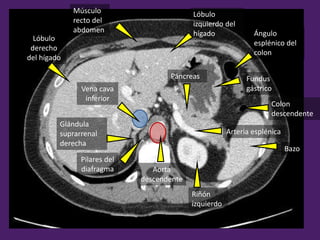

Músculo

recto del

abdomen

Lóbulo

izquierdo del

hígado Ángulo

esplénico del

colon

Bazo

Riñón

izquierdo

Páncreas

Arteria esplénica

Aorta

descendente

Vena cava

inferior

derecho

del hígado

Fundus

gástrico

Pilares del

diafragma

Glándula

suprarrenal

derecha